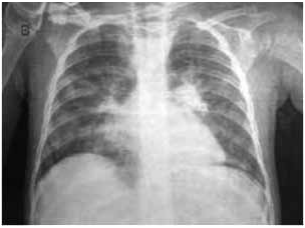

Analise o caso clínico a seguir para responder à questão:

Paciente do sexo feminino, de 65 anos, portadora de hipertensão arterial e dislipidemia mista, chega à sala de emergência com história de dor torácica há três horas, sem fatores de piora. Nega irradiação. Realizou eletrocardiograma mostrado a

seguir, com troponina ultrassensível elevada:

Paciente do sexo feminino, de 72 anos, portadora de nefropatia diabética com disfunção renal grave (clearance de

creatinina de 14 mL/min/1,73 m2) e insuficiência cardíaca de classe funcional II (NYHA), apresenta dor torácica atípica há

uma semana, irradiada para dorso, com melhora em posição sentada e piora ao decúbito. Refere febre baixa e cansaço

progressivo na chegada à UPA. Ao exame físico: PA: 110 × 68 mmHg, FC: 98 bpm, bulhas normofonéticas com atrito

pericárdico audível, sem sopros, ausculta pulmonar limpa. Exames laboratoriais iniciais: ureia: 198 mg/dL; creatinina:

4,8 mg/dL; potássio: 4,9 mEq/L; troponina levemente aumentada, sem elevação dinâmica. Realizou o eletrocardiograma

mostrado a seguir: